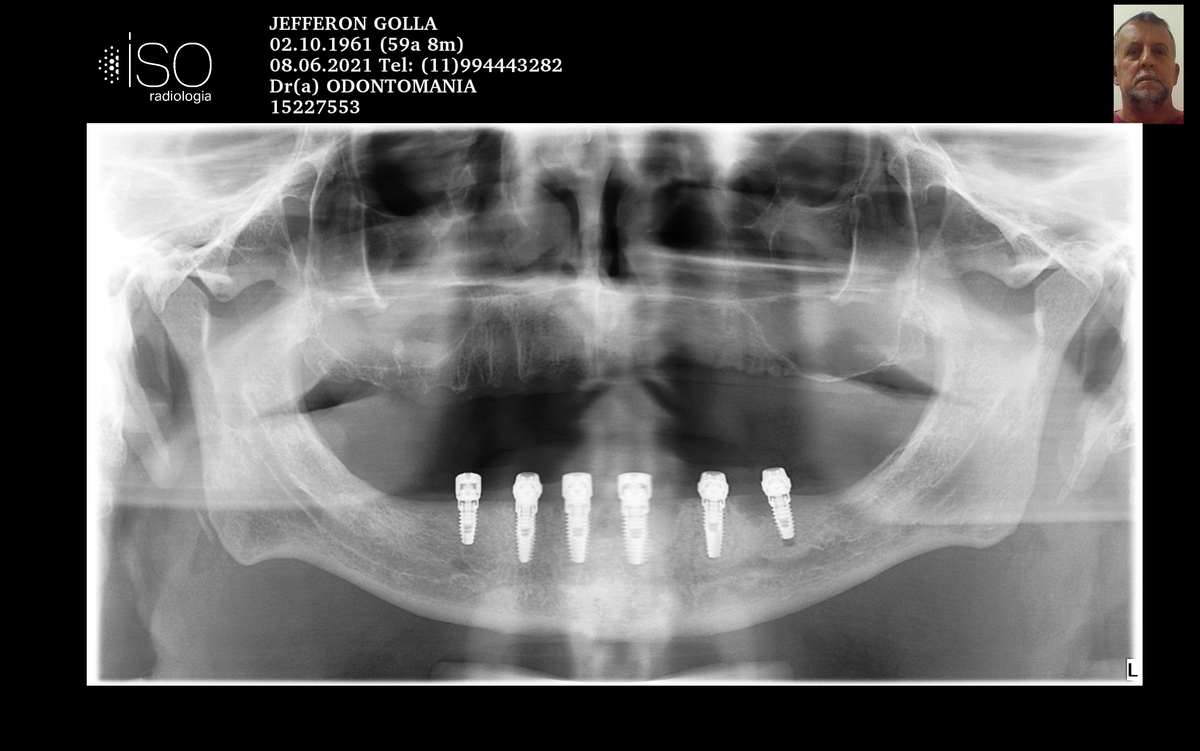

PRÓTESE TOTAL FIXA EM IMPLANTES

J.G.